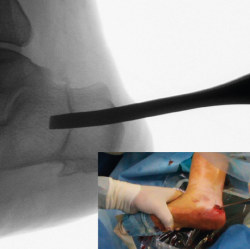

Corrección

Una vez completada, se desplaza la tuberosidad del calcáneo manualmente en la dirección necesaria para la corrección de la deformidad y se introduce un periostotomo a través de la incisión en el escalón que queda tras el desplazamiento para aumentar y mantener dicho desplazamiento. En caso de pie plano valgo, el desplazamiento es medial y se introduce el periostotomo en dirección anterior en la esponjosa del cuerpo del calcáneo para aumentar la traslación (Figuras 7 y 8). En caso de pie cavo varo, el desplazamiento es lateral y se introduce el periostotomo en la esponjosa de la tuberosidad.

Figura 7. Imagen fluoroscópica de la traslación de la tuberosidad con un periostotomo (imagen anteroposterior) y su correspondencia en cirugía.

Se debe mantener la rodilla flexionada para evitar que la tensión del Aquiles nos limite el desplazamiento.

Figura 8. Imagen fluoroscópica de la traslación de la tuberosidad con un periostotomo (imagen axial) y su correspondencia en cirugía.

Osteosíntesis

Una vez comprobado el suficiente desplazamiento en la proyección axial del calcáneo, se fija la osteotomía con 2 agujas de Kirschner sobre las que se introducirán 2 tornillos canulados de un tamaño de entre 5,5 y 7 mm, y se verifica su correcta colocación en la visión lateral y axial fluoroscópica (Figura 9).

Figura 9. Imágenes fluoroscópicas de fijación de la osteotomía con agujas de Kirschner y tornillos canulados en anteroposterior y axial del calcáneo.